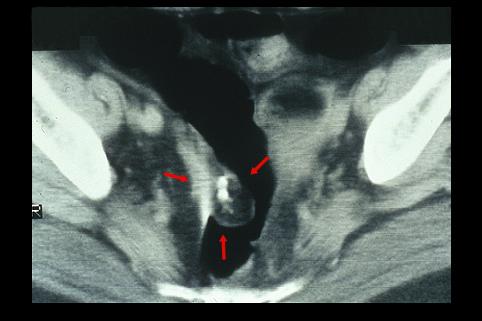

疾患(病理主体)の分類腫瘍様病変/近接臓器からの浸潤

部位(臓器別)大腸/直腸

検査方法CT

病変の最大径(ミリ)30〜34